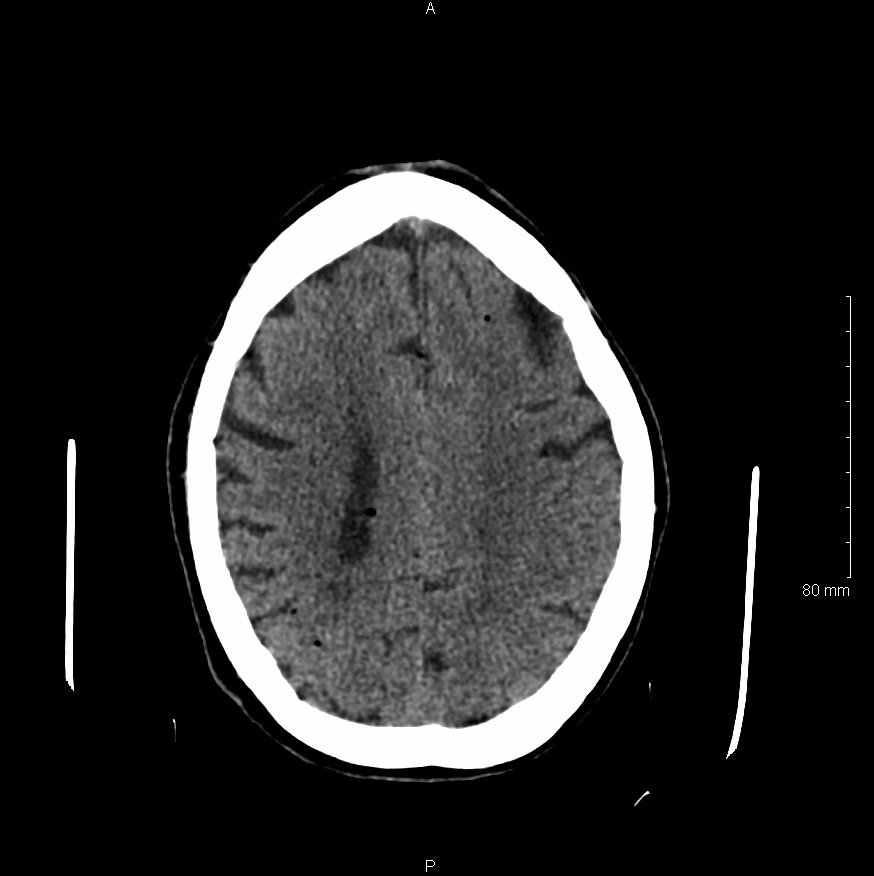

Physical examination revealed an obtunded female with sonorous respirations who withdrew from painful stimuli. Her blood pressure was 169/100 mm Hg, her heart rate was 104/min, and her respiration rate was 21/min. Further neurological examination identified left sided facial droop, left horizontal gaze palsy, and positive Babinski sign. Rapid sequence intubation was performed and a code stroke was called. The patient underwent diagnostic non-contrast computed tomography which revealed diffuse hypodense lesions consistent with an air embolism.

Significant findings:

Non-contrast head computed tomography (CT) demonstrates multifocal bilateral hypodense lesions (white arrows) representing air emboli. Note the lesions are located in the intra-axial distribution which indicates an underlying vascular origin.